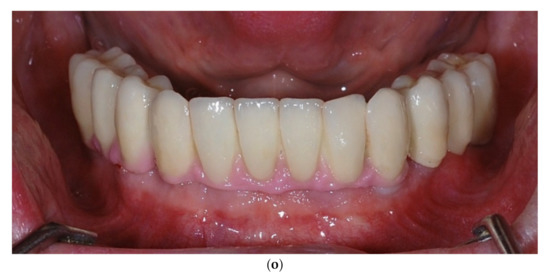

Intraoral view aspects and CBCT images of the implant sites, from a patient included in the test group, are presented in Figure 1a–o (reconstruction of the implant sites by S-GBR technique with porcine-derived xenograft material).

Figure 1.

(a) A.C., aged 65. Preoperatory intraoral view. (b) Preoperative CBCT images and alveolar bone parameters measured with Sidexis XG/ DVT (Densply/Sirona) software. (c) Intraoral view after the insertion of osteosynthesis screws and implants. (d) Intraoral view after the mandibular alveolar reconstruction with S-GBR technique and porcine xenograft. (e) Postoperative intraoral view after wound suture and temporary loading. (f) Alveolar bone width values measured at baseline (left) and at 6 months follow-up with Sidexis XG/ DVT software (Densply/Sirona). (g) Alveolar bone width values measured at baseline (left) and at 6 months follow-up with Sidexis XG/ DVT software (Densply/Sirona). (h) Alveolar bone width values measured at baseline (left) and at 6 months follow-up with Sidexis XG/ DVT software (Densply/Sirona). (i) Alveolar bone width values measured at baseline (left) and at 6 months follow-up with Sidexis XG/DVT software (Densply/Sirona). (j) Alveolar bone osteodensity values measured at baseline (left) and at 6 months follow-up (right) (implant site 4.1). (k) Alveolar bone osteodensity values measured at baseline (left) and at 6 months follow-up (right) (implant site 4.5). (l) Alveolar bone osteodensity values measured at baseline (left) and at 6 months follow-up (right) (implant site 3.2). (m) Alveolar bone osteodensity values measured at baseline (left) and at 6 months follow-up (right) (implant site 3.5). (n) Preloading intraoral view. (o) Postloading intraoral view.